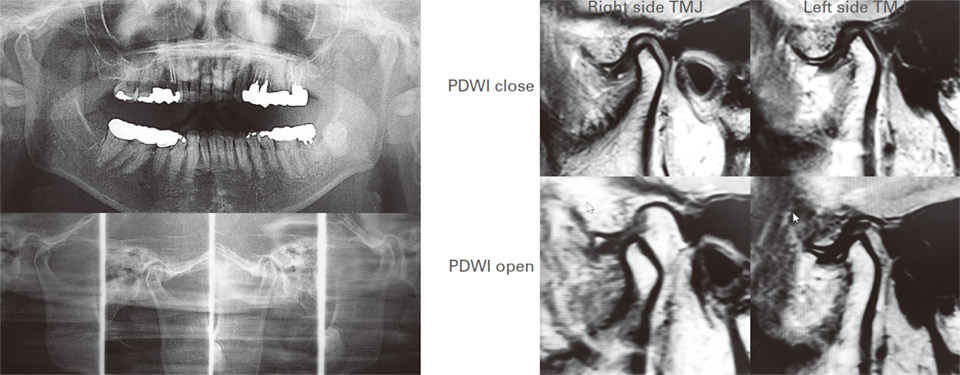

現症:初診時、無痛自力開口量は23mm、MRI画像診断にて両側顎関節に非復位性の関節円板前方転位と下顎頭に骨変形を認める(図3)。診断:両側顎関節症、関節円板障害(非復位性関節円板前方転位)、両側変形性顎関節症。

臨床経過:骨変形が開口障害に影響していることが考えられること、開口訓練を主体とした保存的治療が奏効しなかったことから、全身麻酔下での両側顎関節授動術の適応と考えられたが、患者の同意が得られなかったことにより、徒手および従来型の開口訓練器を用いた開口訓練の再指導を行った。上記治療を行い1ヵ月後に無痛自力開口量は27mmとなったが、それに続く6ヵ月間ではそれ以上の改善は得られなかった。MRI検査にて両側顎関節症、関節円板障害(非復位性関節円板前方転位)、両側変形性顎関節症が確認され(図3)、新型開口訓練器の使用を開始した。開口訓練器の下顎前方滑走誘導量の設定は8mmとし、無痛自力開口量27mm、強制開口量27mmから訓練を開始した(図4)。

図3 症例1。MRI上で両側顎関節に非復位性関節円板前方転位と下顎頭の骨変形を認める。